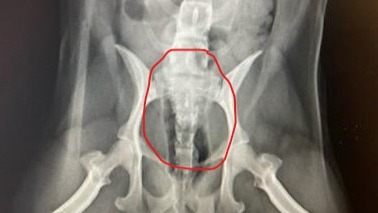

His most recent comprehensive exam showed he currently has over 30 stones in his bladder (see attached photos). At this point, due to his previous four surgeries, our only option for him is to have a Scrotal Urethrostomy surgery. This surgery aims to widen the urethral opening to allow the passage of stones. The goal of this surgery is to get him relief from undergoing continuous surgeries and give him a chance at a healthy and happy life. Unfortunately, his surgery will cost $6000 as his insurance does not cover it.